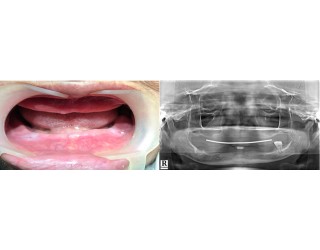

Bác sĩ Nguyễn Văn Hoàng Minh là người sáng lập ra Nha khoa Minh Nguyên. Là thành viên hiệp hội Implant thế giới ICOI (International Congress of Oral Implantologists thành lập từ năm 1972 tại Hoa Kì), Bác sĩ Nguyễn Văn Hoàng Minh đã tu nghiệp các nước Mỹ, Pháp, Đức,Thụy Sĩ, Hàn Quốc… và có hơn 25 năm kinh nghiệm chuyên cấy ghép Implant và chỉnh hình răng thẩm mỹ.